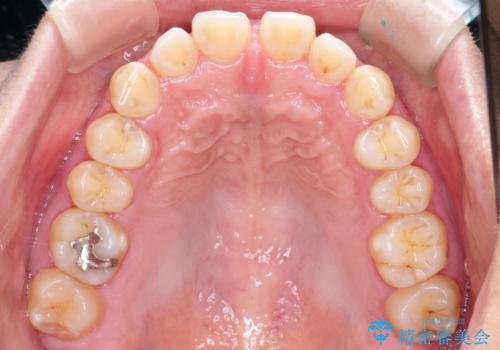

【インビザライン】前歯のすきまを閉じたい

- 前歯の隙間を主訴に来院されました。

インビザライン にて治療を行い、歯並びを改善することができました。